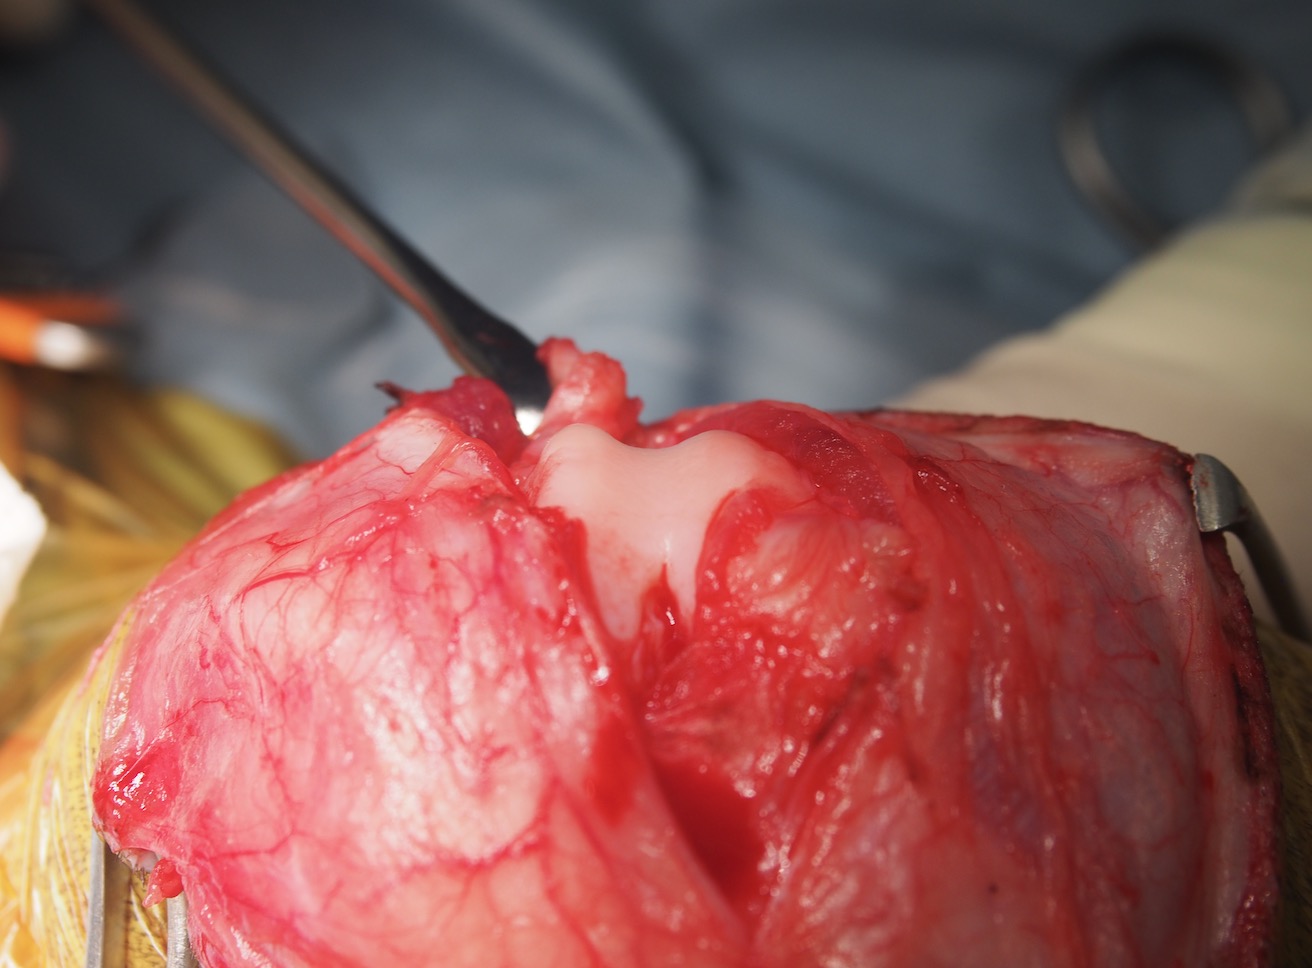

滑車造溝術(ブロック状造溝術)

滑車造溝前

滑車溝が十分に形成されておりません

滑車造溝後

軟骨を切り取り、やすりをかけて十分な滑車溝を形成しました